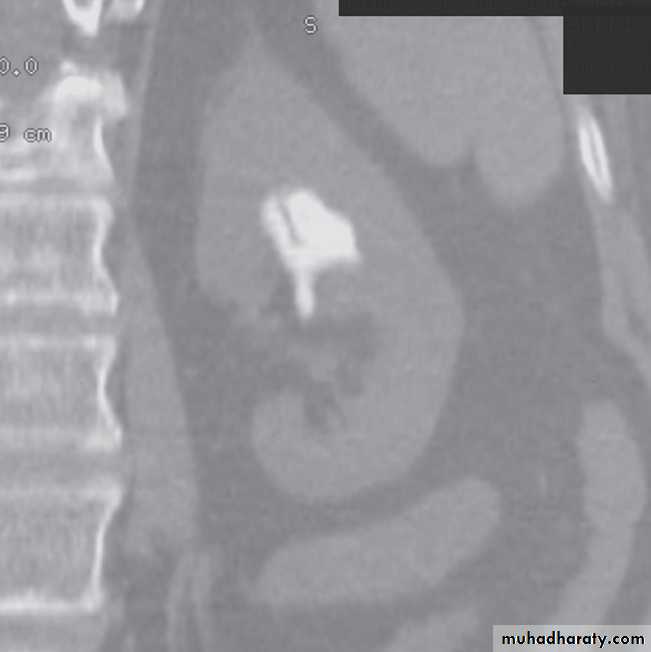

Computed tomography without intravenous contrast medium is exquisitely sensitive for the detection of calculi.

It is used in place of IVU for the detection and precise anatomical localization of stones prior to treatment in most centres

Computed tomography is now widely used to evaluate urinary tract obstruction .In acute obstruction, non-contrast enhanced CT sensitively demonstrates calculi and the unopacified, dilated collecting system can frequently be traced down to the point of obstruction .

At CT:

-A typical simple renal cyst is a spherical mass with an imperceptible wall . The interior of the cyst is homogeneous with attenuation values similar to water.

-Renal cell carcinomas are approximately spherical and often lobulated .With density similar to renal parenchyma or slightly less with often seen some areas of necrosis & calcification .